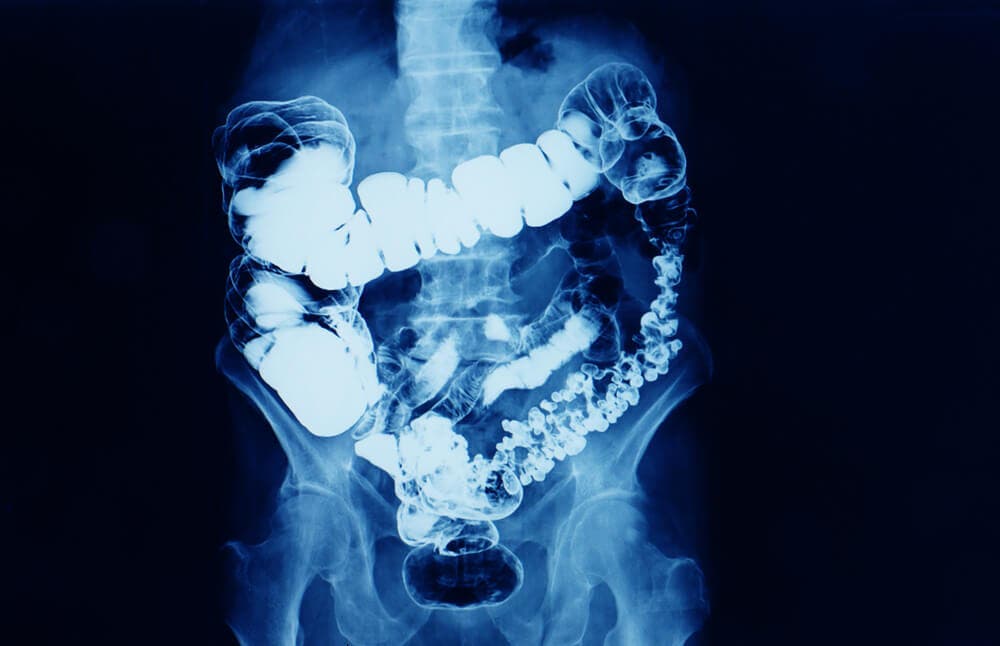

En general, se habla de estreñimiento cuando disminuye la frecuencia de las deposiciones. El estreñimiento es un síntoma de que el tránsito intestinal está disminuido por alguna causa.